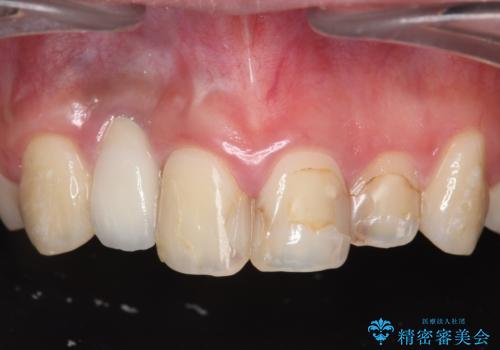

前歯の虫歯 オールセラミック治療

【オールセラミッククラウン】他院で入れた被せものがすぐとれる